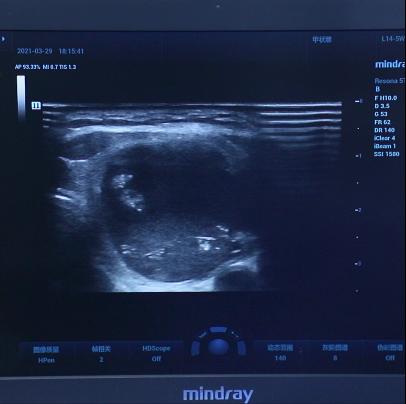

到院后先为李女士安排了 甲功八项和四维弹性成像 检查,检查结果发现结节后方回声衰减,其内可见微钙化灶。